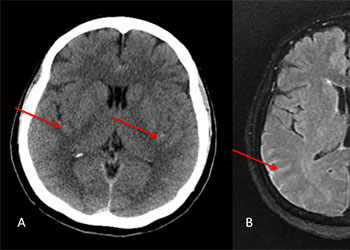

Brain:

Cerebellar Hemangioblastoma

Author: Michael Brisman M.D., F.A.C.S., Read More!